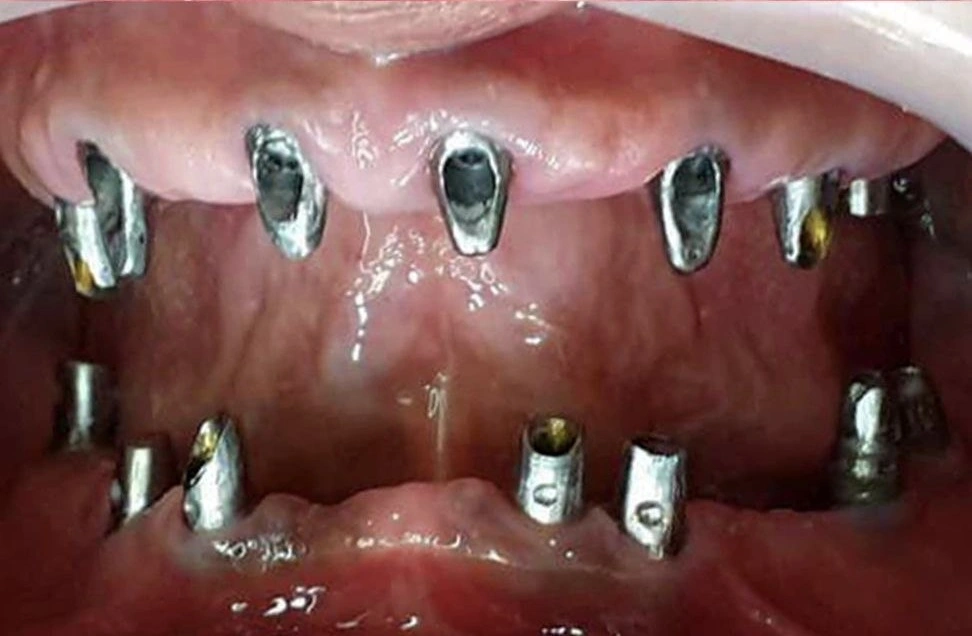

- کاشت پایه ایمپلنت: قرار دادن پایه تیتانیومی در استخوان فک به صورت هم زمان.

- نصب روکش موقت: در صورت مناسب بودن شرایط فک، روکش موقت بلافاصله قرار می گیرد.